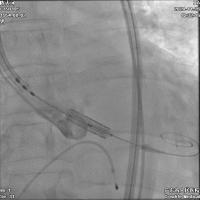

术中建立双侧股动脉入路,以右股动脉为主,送入导丝顺利跨瓣进入左室,先行球囊预扩张,处理主动脉瓣环钙化;后续沿已建立的导丝路径,送入Edwards Sapien 3球囊扩张式主动脉瓣膜置换系统,在推送的过程中,一边调弯一边缓慢推送,保证安全过弓并成功完成跨瓣。

随后将Edwards Sapien 3瓣膜精确定位至预期位置,以180次/min快速起搏,保证1:1夺获,使收缩压降至50 mmHg,迅速释放瓣膜,整个过程一气呵成。